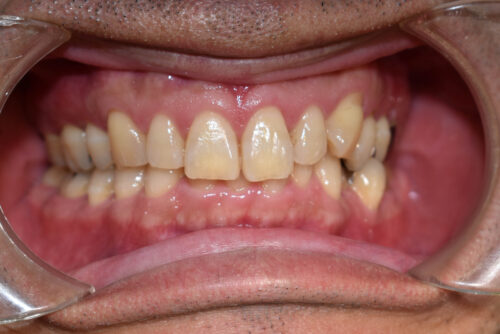

初診時年齢 46歳 男性

歯のでこぼこ(叢生)

左下第二小臼歯が 外に飛び出している

と

頬側転位

を主訴に

池袋よりひとつ隣駅の東京都豊島区大塚駅すぐの大塚たまみ矯正歯科へ

いらっしゃいました。

かみ合わせが深く

がたついている 状態でした。